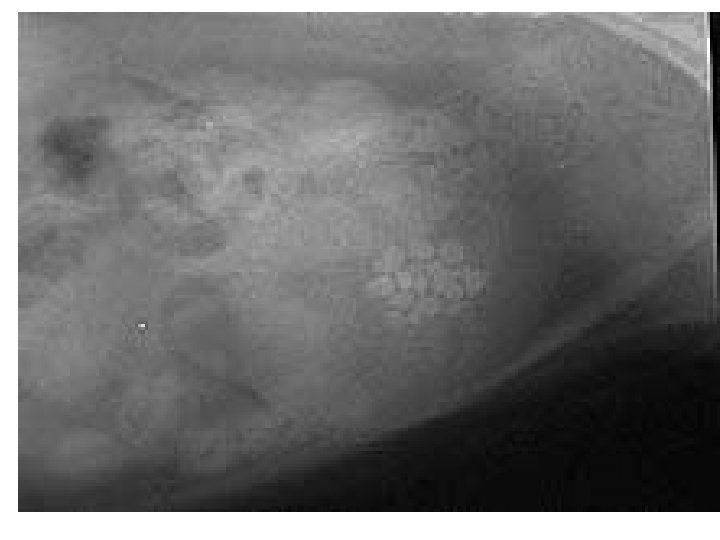

Large numbers of calcium oxalate crystals seen in the urine may indicate a predisposition to oxalate urolithiasis.

Calcium oxalate stones can not be dissolved by diet and must be surgically removed. 50% of animals who undergo cystotomy sx will redevelop stones within 3 years.

Cystotomy :